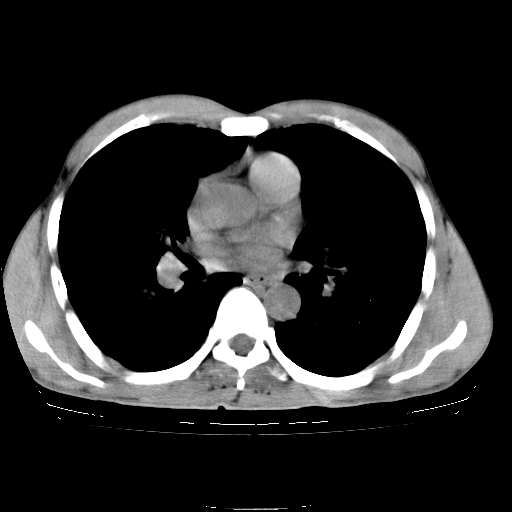

以下是引用yangyudong333在2008-4-29 5:38:00的发言:[br]比较典型的矽肺结节.支持[br]诊断依据:[br] 1.x线表现:[br] ①典型矽肺为多发直径 1~3mm 小结节,即矽结节,由胶原纤维和硅尘构成,可融合成团块,好发于上肺。[br] ②团块周围常有肺大泡。[br] ③胸内淋巴结增大、钙化。如肺门淋巴结呈蛋壳样钙化有助于与其他尘肺区别。[br] ④胸膜常广泛粘连、增厚。[br] 2.ct表现[br] ①两肺散在大小较为一致的小结节影,其密度较高,边界清楚。[br] ②小结节可融合为较大团块影,直径约 1cm ,甚至可达 10cm以上,易发生在上叶。[br] ③小结节周围常并有小叶中心气肿或弥漫性肺气肿。

以下是引用liuyue在2008-4-28 22:30:00的发言:[br]比较典型的矽肺结节.[br]请结合临床及化验除外矽肺合并肺结核之可能.